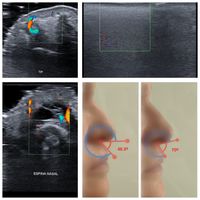

RINOMODELACIÓN ECOGRÁFICA